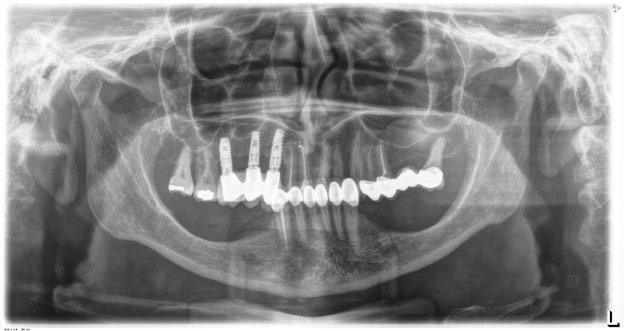

Figura 8. En la radiografía inicial ya se hace evidente que los sectores posteriores mandibulares tienen una escasa altura ósea residual y podemos ver desajustes en la prótesis sobre implantes superior del primer cuadrante.

Figura 16. Radiografía de la colocación de los implantes y la prótesis de carga inmediata horas después de la cirugía.